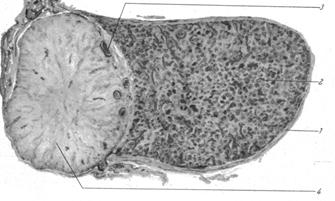

Будучи анатомически единым органом, гипофиз делится на две доли, имеющие различное происхождение, строение и вырабатывающие различные гормоны (рис. 12). Передняя доля развивается из эпителия ротовой бухты и носит название аденогипофиз. Она крупнее задней доли и состоит из бугорной и промежуточной частей. Задняя доля развивается из второго мозгового пузыря — будущего промежуточного мозга — и носит название «нейрогипофиз».

Рис. 12. Гипофиз человека:

1 — капсула, 2 — передняя доля, 3 — фолликул промежуточной доли,

4 —задняя доля